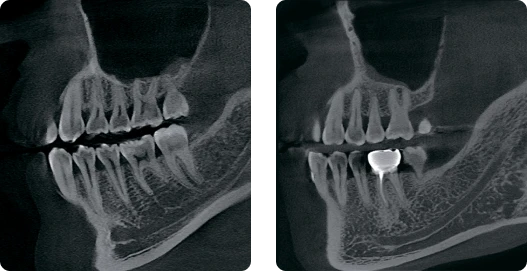

КЛКТ

Когда вам нужно сделать снимок быстреe…

До 4,9 секунды сканирования и 4х секунд 3D-реконструкции!

Когда вам нужно увидеть больше деталей…

До 70 мкм в Endo режиме!

Когда вам нужно увидеть больше анатомии…

Область до 16 см реконструируется за 6 секунд!

Сверхвысокое разрешение

Когда вам нужна очень точная детализация…

До 70 мкм режим сканирования для эндодонтии.

КТ-изображение с высоким разрешением в определённой области.